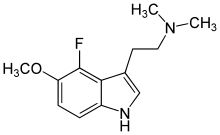

Substituted tryptamines, or serotonin analogues, are organic compounds which may be thought of as being derived from tryptamine itself. The molecular structures of all tryptamines contain an indole ring, joined to an amino (NH2) group via an ethyl (−CH2–CH2−) sidechain. In substituted tryptamines, the indole ring, sidechain, and/or amino group are modified by substituting another group for one of the hydrogen (H) atoms.

| 6-Fluoro-5-MeO-DMT | artificial | 5-OCH3,6-F | CH3 | CH3 | 5-methoxy-6-fluoro-N,N-dimethyltryptamine | |